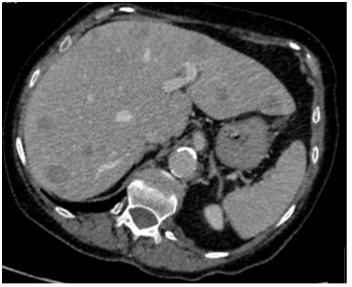

Our patient was a 79-year old female with severe progressive chronic obstructive pulmonary disease (COPD) on home oxygen, type 2 diabetes, hypertension and angina. She presented with type 1 respiratory failure and chest pain in December 2015. A computed tomography pulmonary angiogram (CTPA)4 months prior to this admission, showed no pulmonary embolism but did show a solitary liver lesion (Figure 1), measuring 2.5cm x 2.8cm that was suspicious for metastasis. A subsequent contrast-enhanced staging CT abdomen and pelvis demonstrated multiple liver metastases (Figure 2) with a 5.5cm solid-cystic lesion arising from her left kidney. After discussion with the Hepatobiliary multidisciplinary team (MDT), she underwent a percutaneous biopsy of the liver lesions, which showed metastatic carcinoma of indeterminate primary. She was seen by our Oncologists and was deemed suitable only for palliative treatment at this stage due to a presumed metastatic renal cancer and her multiple co-morbidities.

Figure 1: CTPA showing solitary liver lesion in August 2015.